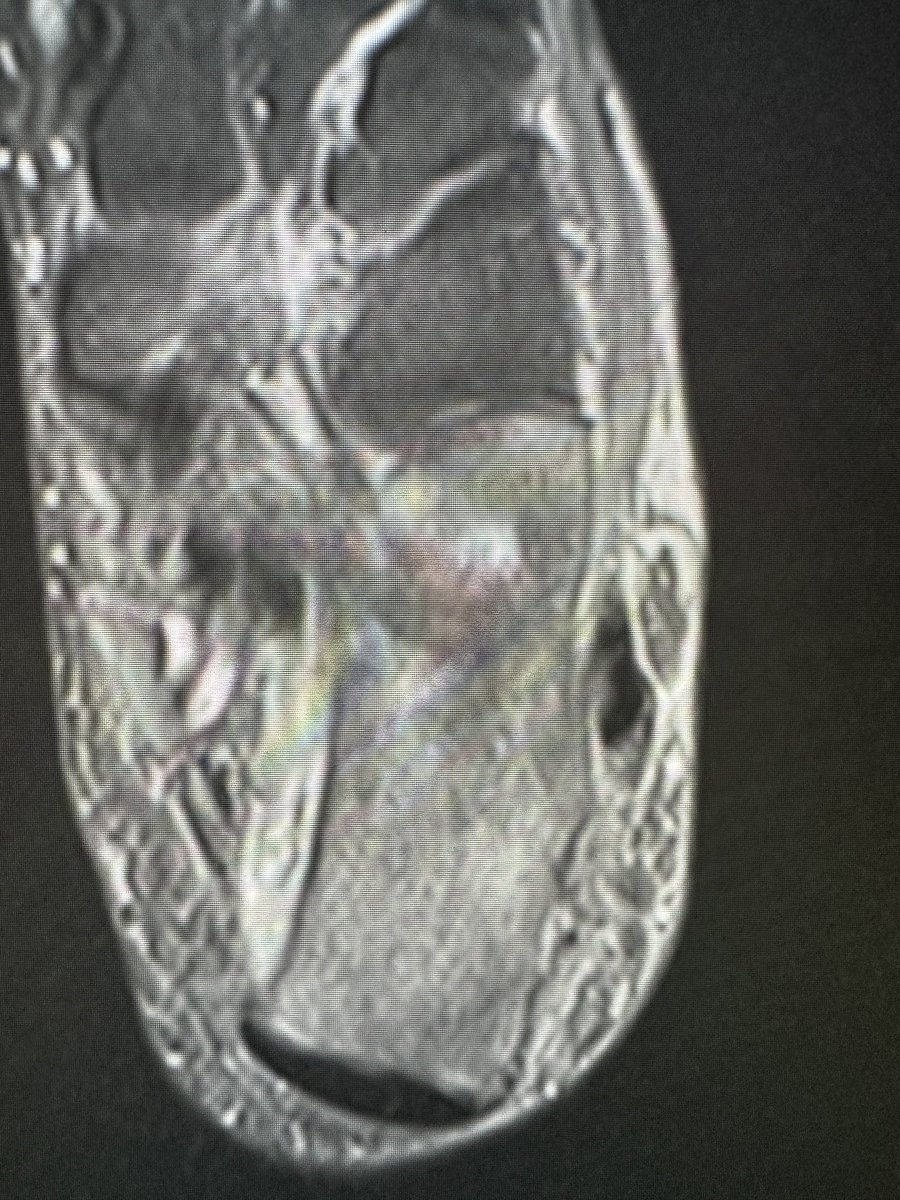

Nice example of a haglund deformity, insertional tendinopathy and partial tear with reactive bursitis

RJ tweet mediaRJ tweet media